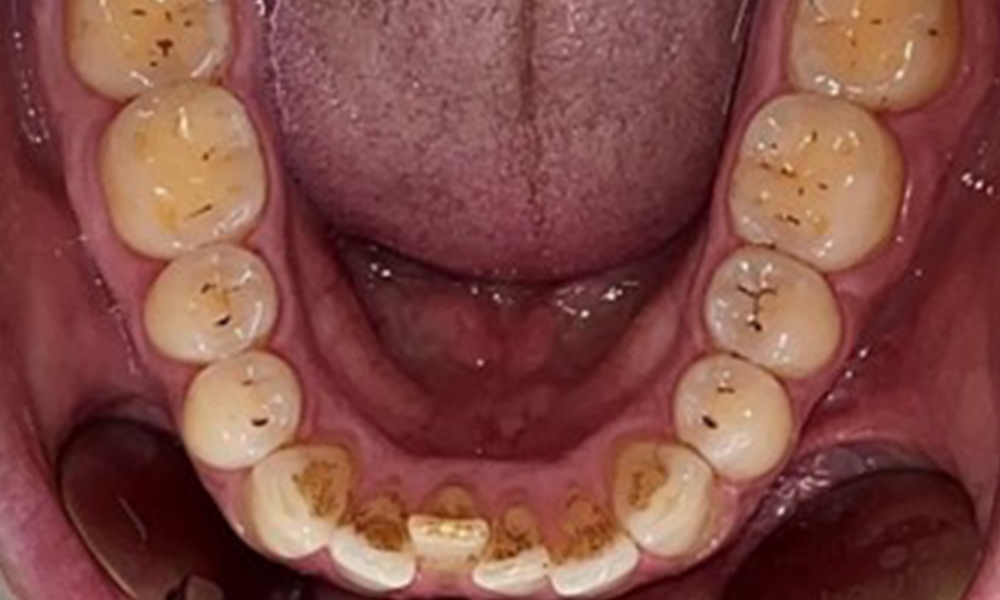

Okklusalansicht Unterkiefer

Abb. 4: Okklusalansicht Unterkiefer, © Dr. R. Krapf

Dental zeigt sich ein vollbezahntes Gebiss mit 28 Zähnen. Auffällig sind Erosionen und Attritionen

(Abb. 4, Abb. 5). Der Patient trägt seit vielen Jahren nachts eine Schiene mit adjustiertem Aufbiss aufgrund Bruxismus. Die Erosionen sind auf den langjährigen Konsum isotonischer Getränke zurückzuführen. Parodontaler Knochenverlust und aktive kariöse Läsionen sind nicht vorhanden.